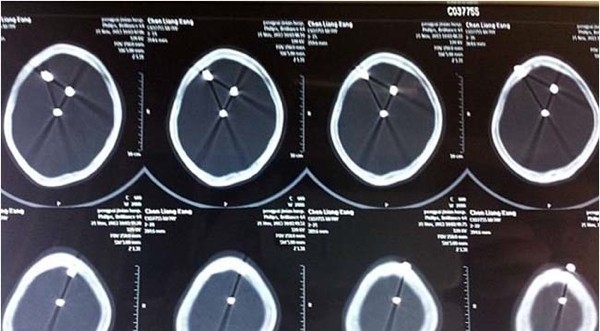

Çivilerin başları açıkça dışarıdan bile görünürken doktorlar Çinli adamın röntgenini çekti ve 3 koca çivi ile karşılaştı.

Hemen ameliyata alınan adamın başındaki çiviler teker teker çıkarıldı.